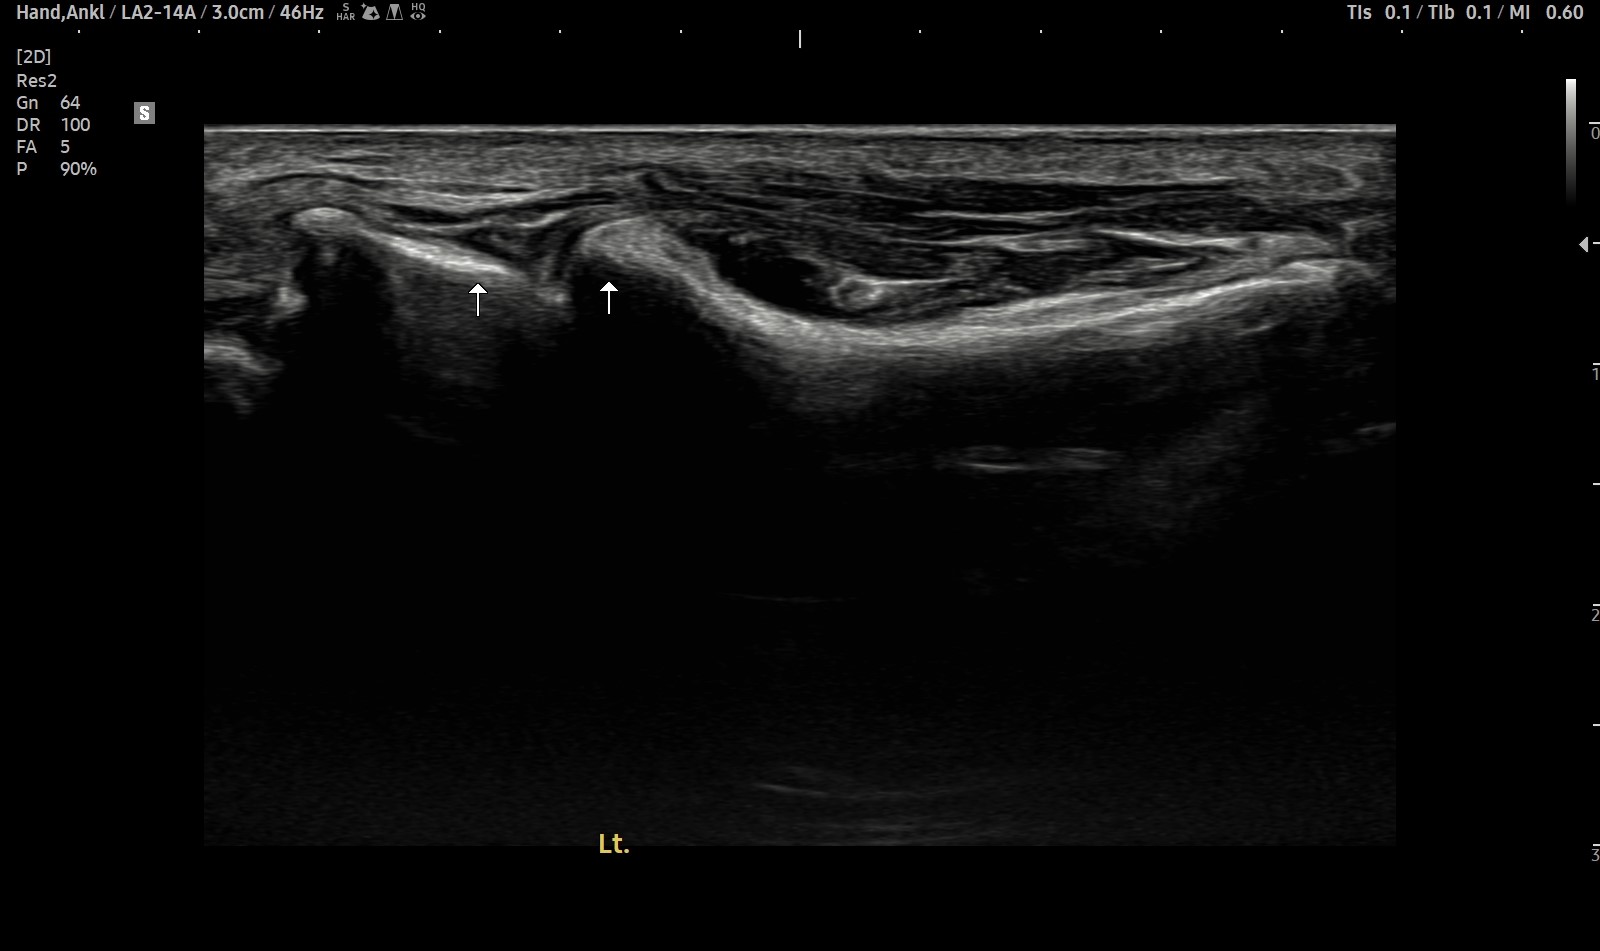

- 치료기간 : 25 . 5 . 7 ~ 25 . 8 .12

- 치료횟수 : 4cycle(20) 회

치료전

치료후